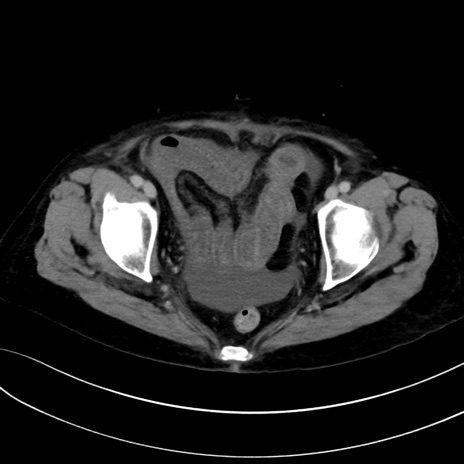

症例13 CT(横断像)1日半後